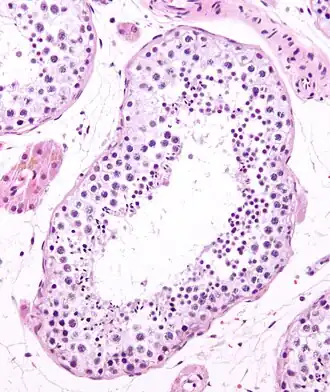

Seminiferous tubule in cross-section (large tubular structure – center of image) with sperm (black, tiny, ovoid bodies furthest from the outer edge of the tubular structure). H&E stain.

The epithelium of the tubule consists of a type of sustentacular cells known as Sertoli cells, which are tall, columnar type cells that line the tubule.

In between the Sertoli cells are spermatogenic cells, which differentiate through meiosis to sperm cells. Sertoli cells function to nourish the developing sperm cells. They secrete androgen-binding protein, a binding protein which increases the concentration of testosterone.